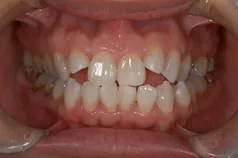

[症例]

矯正治療を行っています。

治療前は上下の歯が反対になっている所もあり、上の歯の真ん中から2本目の歯は矮小歯と言って、平均より小さな歯のため上唇が引っ込んで見えます。

インビザラインでマウスピース矯正後、オフィスホワイトニングを行い、矮小歯はラミネートベニアで修復しました。

綺麗な歯並びになるとともに、上顎の歯列のアーチが広がって、上唇がやや前方に出ることで自然な口元になりました。

[費用・期間・副作用]

- 治療期間: 1年6ヶ月

- 治療回数: 10回

- 費用: 120万円

- デメリット:治療後に矯正の後戻り防止のためのマウスピースを使用しなければならない